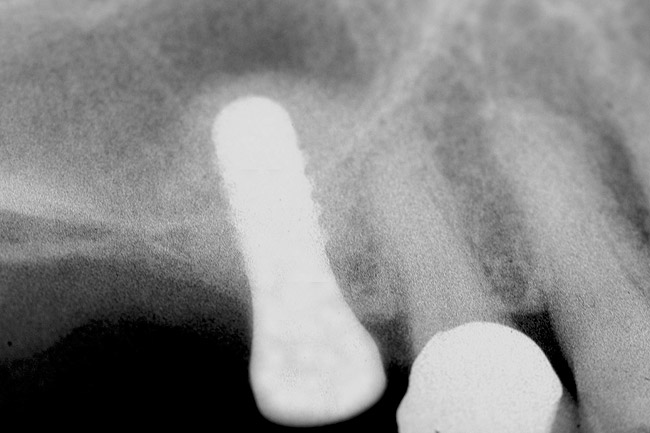

After penetration into the sinus is achieved, a sterile amalgam carrier is used two times to deliver a radiopaque bone substitute into the osteotomy. Then the osteotome used to infracture the subantral floor is lubricated with saline and inserted into the osteotomy until the stop on the osteotome reaches the alveolar crest. This pushes the bone substitute up under the sinus membrane and elevates it. Two more carriers of bone substitute are delivered in the same manner. This will provide around 2 mm of bone height in the sinus (four carriers provide around 2 mm of bone height). A radiograph is then taken to verify that the membrane was elevated, and the bone graft should appear as a dome (Figure 4). If the sinus floor has not been penetrated despite the impression that it was, the bone-graft material may have been pushed laterally. If this occurs, there will be no dome on the radiograph, but, rather, increased osseous density on the lateral aspect of the osteotomy. If this occurs the osteotomy needs to be deepened.

Figure 4  After infracturing the subantral wall with a 3.5-mm osteotome, bone was added and the presence of a dome was confirmed with a radiograph.

Figure 4

Figure 10  The osteotomy was completed with the 2.1-, 2.8-, and 3.5-mm twist drills without penetrating into the sinus. After infracturing the subantral wall with a 3.5-mm osteotome, bone was added and the presence of a dome was confirmed with a radiograph.

Figure 10